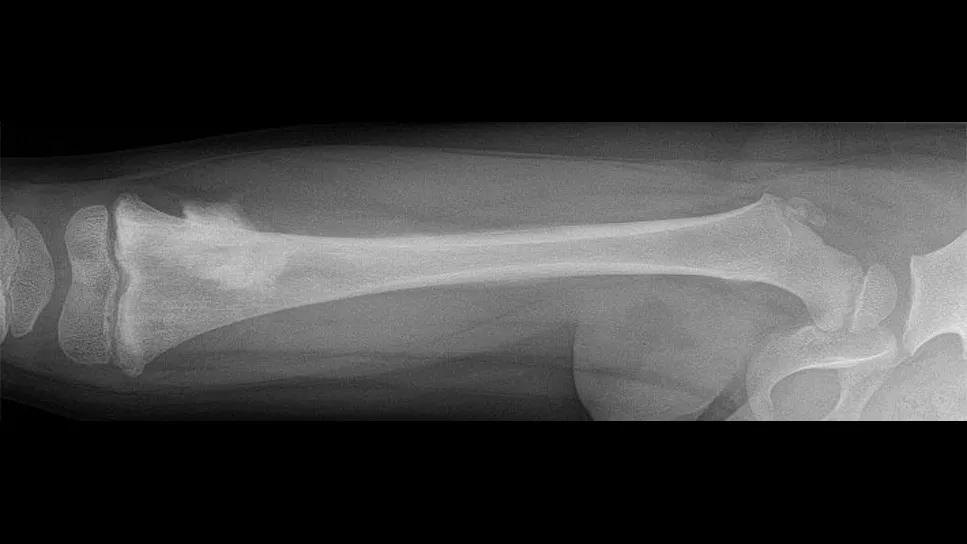

X-ray showing leg bones